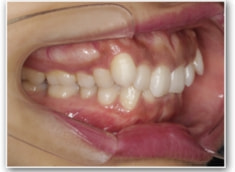

治療後